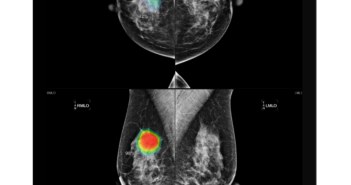

의료 인공지능(AI) 기업 루닛은 강북삼성병원과 유방촬영술 AI 영상진단 솔루션 ‘루닛 인사이트 MMG’ 공급 계약을 체결했다고 1일 밝혔다. 루닛 인사이트 MMG는 딥러닝 기반 AI 기술로 유방촬영술 영상을 분석해 유방암 의심 부위를 신속하게 탐지하고 시각화하는 솔루션이다. 특히 유방 조직의 밀도(Density)에 따라 발생할 수 있는 판독 오류를 최소화해 정확한 진단을 돕는다. 이번에 루닛 제품을 도입하는 강북삼성병원은 올해 '미래헬스케어본부'를 신설하여 ICT 융합 디지털 헬스케어 선도병원으로의 도약에 나서고 있다. 이번 AI 솔루션 도입은 이러한 노력의 일환으로, 유방암 검진 및 치료 과정에 AI를 접목해 혁신적인 디지털 의료 서비스 제공을 목표로 한다. 루닛은 강북삼성병원 의료진을 대상으로 AI 솔루션 관련 교육 및 기술 지원을 지속적으로 제공하여 효과적인 활용을 지원할 계획이다. 서범석 루닛 대표는 "강북삼성병원 같은 주요 상급종합병원에 루닛 AI가 도입된 것은 의료AI 기술의 확산에 있어 중요한 이정표"라며 "의료 분야에서 AI의 역할이 점차 확대되는 가운데, 앞으로도 지속적인 R&D 투자와 임상 연구를 통해 더욱 정교하고 신뢰할 수 있는 AI 솔루션을 개발해 나가겠다"고 말했다. 관련 기사 더보기 https://www.venturesquare.net/929718